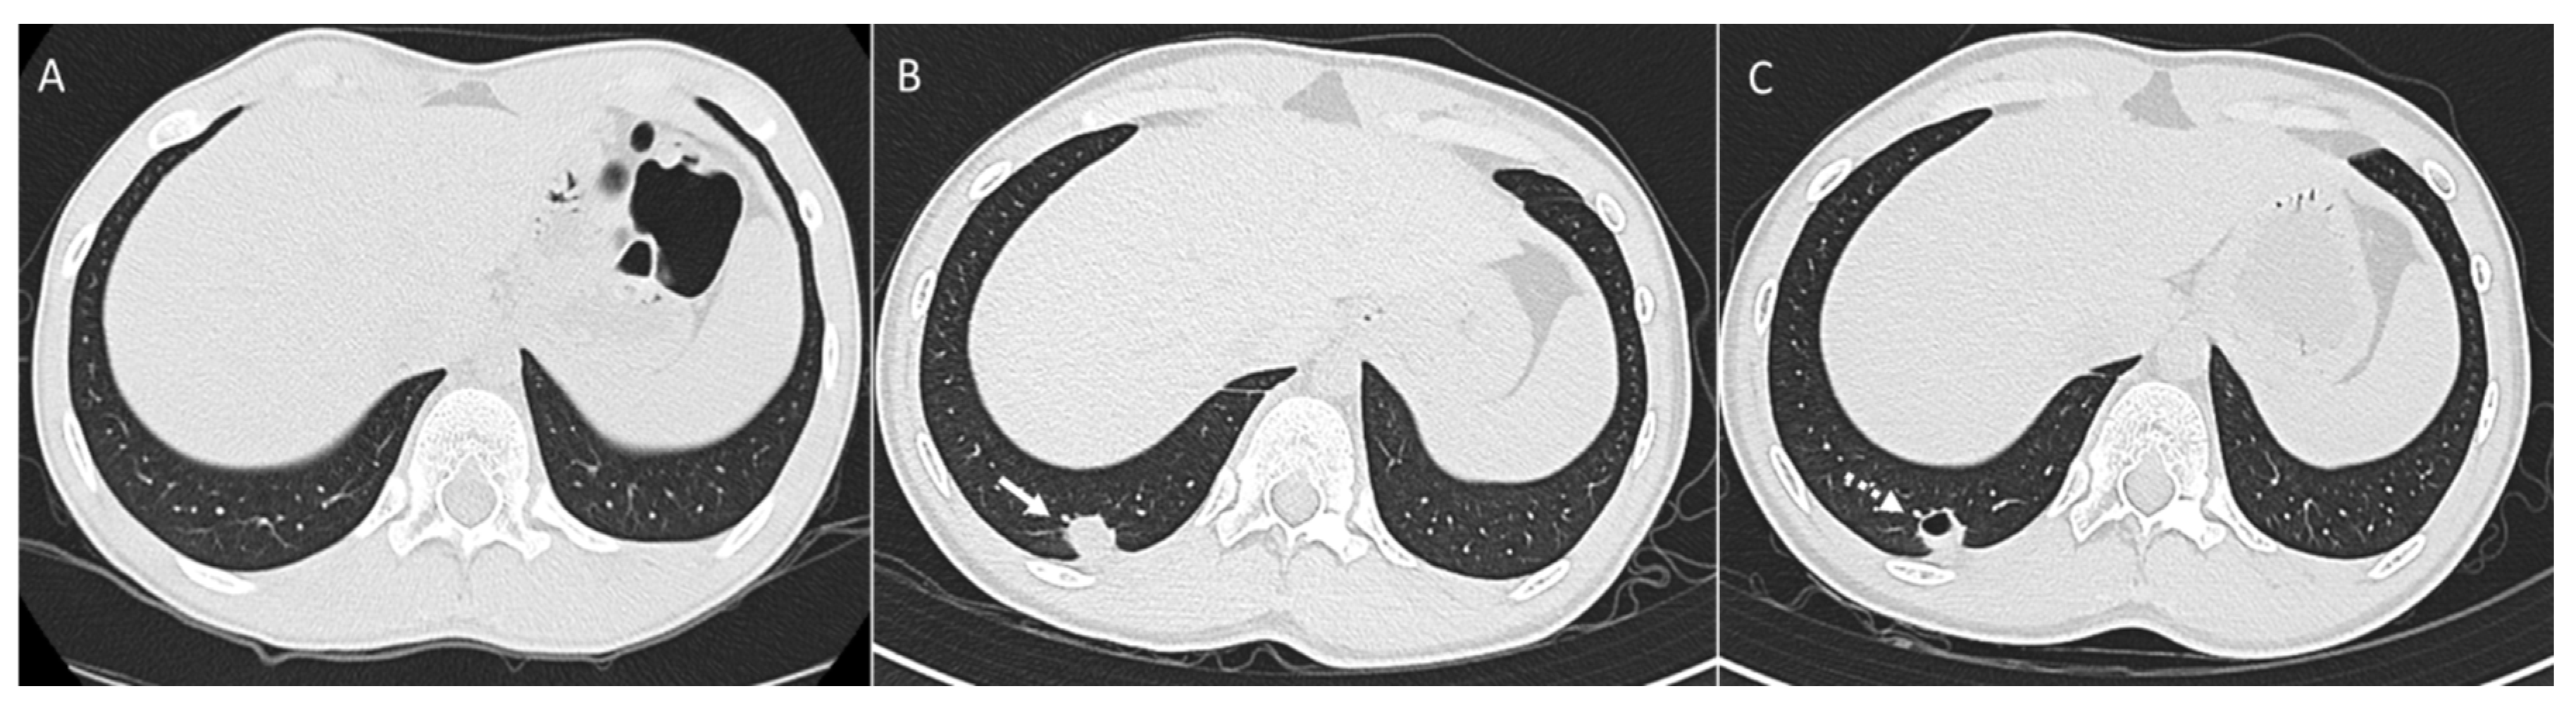

3. Pleura